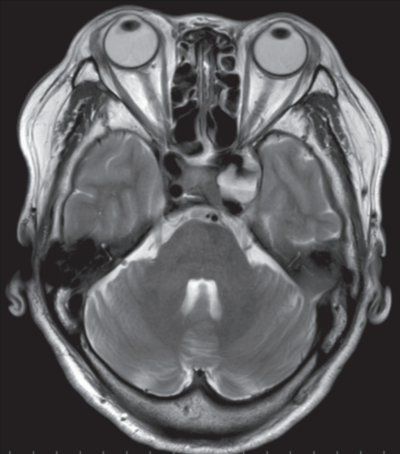

66 歳の女性。左方視時の複視と羞明を主訴に来院した。 1 か月前から複視を自覚し、 2 日前から左眼の羞明が出現したため受診した。

意識は清明。 体温36.4 ℃。脈拍 72/分、整。血圧 128/86 mmHg。呼吸数 14/分。頭部単純 MRI T2強調像と選択的左内頸動脈造影側面像を別に示す。